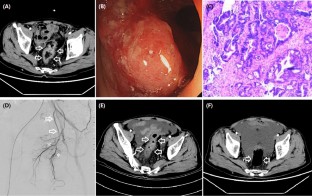

Fig. 2